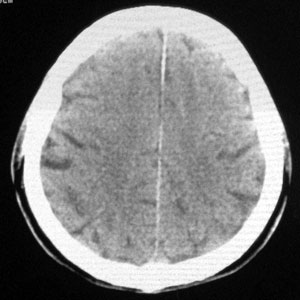

男性,65岁,头疼。 看看这大脑镰,ct值约83hu .

楼主的意思是让我们看大脑镰串珠样钙化,虽然ct值83hu ,也应该是钙化.(循环渐进).